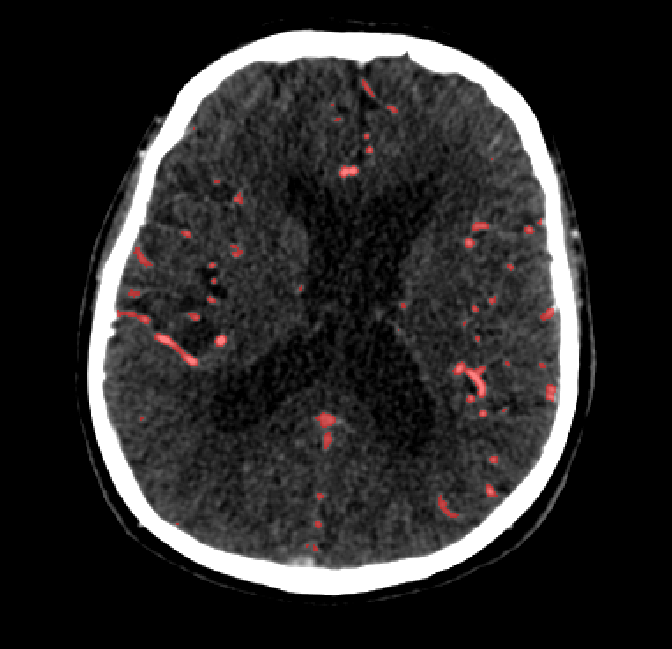

After fine-tuning, the two pre-train conditions appear to have little or no difference in terms of qualitative performance at the vessel segmentation task. However, when compared to the models trained only on real data, there are noticeable differences. Throughout Figures 4.3-4.9, the model pre-trained on scans with original CT noise is to be taken as representative of segmentation performed by the Perlin noise pre-training condition. Images showing the hand-labeled ground truth, as well as the unlabeled slice, are presented for comparison.

Figure 4.3: Segmentation on internal carotid arteries. Unaltered image (left). No pretrain model (mid-left). Fine-tuned model (mid-right). Hand-labeled ground truth (right).

For vessels in the center of the head, all model types appear to accurately segment vessels. In certain cases, the models appear to learn to correctly avoid segmenting pieces of bone that could, in terms of shape and contrast, easily be confused with large vessels. An example of this can be seen in the frontal section of Figure 4.6.

The models appear to have a hard time segmenting vessels close to the skull surface. The model trained exclusively on patient data appears to struggle far more for these types on conditions than the fine-tuned models. Figure 4.8 shows an example of the fine-tuneds model having close to no trouble segmenting vessels near the left side of the skull, while the baseline model suffers heavily from false negatives. To lesser degree, this effect can also be observed in the frontal lobe of Figure 4.9 In the other hand, Figure 4.7 presents an example of both models failing to segment vessels near the top of the skull.

In the other hand, it should be noted that fine-tuned models suffered from false positives more often than models with no pre-training. The fine-tuned models appeared to occasionally segment regions near the skull, which although similar in intensity to vessels, had no resemblance in terms of shape. Examples of this are seen in Figure 4.4 near the occipital bone and near the right temporal bone. Examples of oversegmentation were observed to happen commonly around the internal carotid arteries. This is likely due to the amount of contact surface between the artery and the surrounding bone. There was also a tendency for all model conditions to segment bone regions that were similar in shape to large vessels (Figures 4.3 and 4.4). Bone structures in such regions have similar pixel intensities to the arteries transporting contrast material, which could explain the source of confusion for a model.

To our surprise, the models were able to occasionlly segment the shape of the internal carotid arteries correctly despite no boundary being visible to the naked eye between the vessel wall and the surrounding bone structure. An example of this can be seen in the fine-tuned model in Figure 4.3.